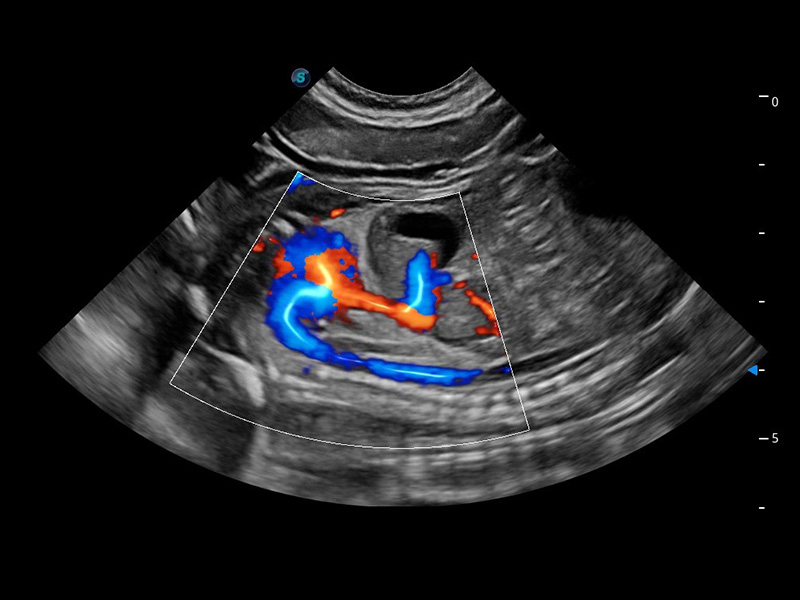

ProPet 60 作为一款高端台式动物超声设备,为动物医生的日常诊断提供了一系列贴合动物临床需求、解决临床实际问题的高级成像功能。凭借全系列高清探头,满足医生对腹部、心脏、生殖、浅表、肌骨等成像的所有需求,切实帮助您提升检查效率,提高诊断信心。

兽用彩色多普勒超声诊断系统

动物是人类最亲密的朋友和最值得信赖的伙伴。球速体育入口也一直致力于探索动物专用的超声影像解决方案。 全新推出的ProPet系列,是球速体育入口在动物超声影像智能化、专业化、精准化的一次跨越式革新。动物不能用言语来表述自己的不适,通过超声影像,ProPet系列搭建了动物医生与不同物种沟通的“桥梁”,为动物医生注入了“治愈之力”。